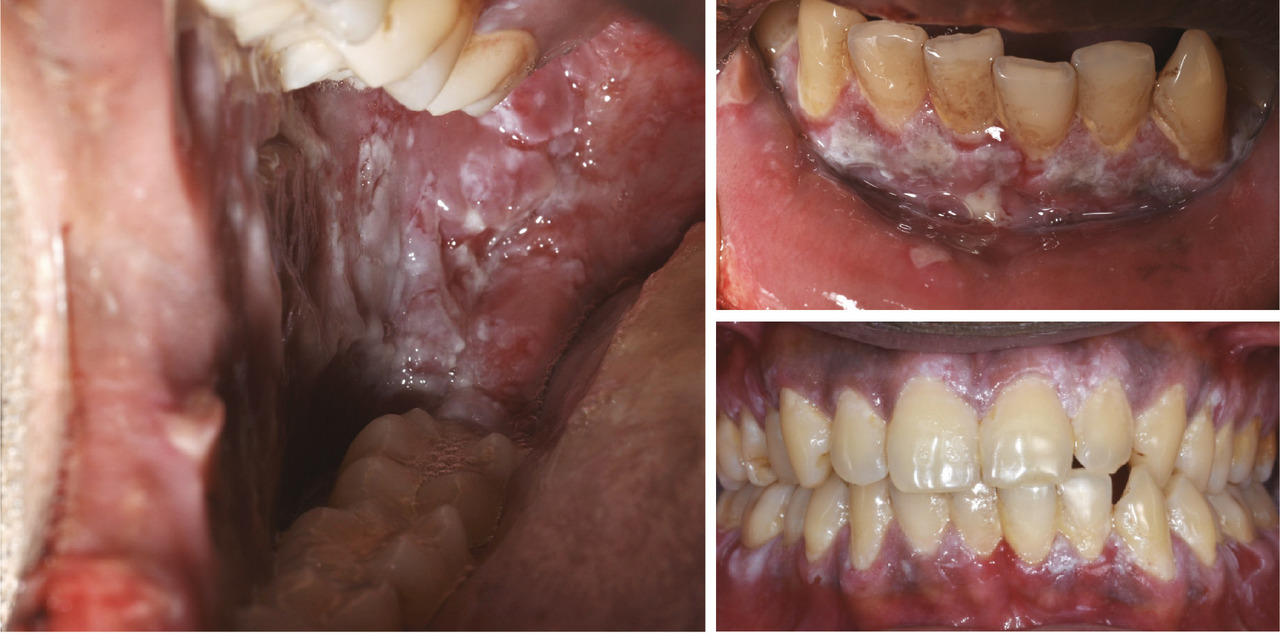

Le pemphigus vulgaire est caractérisé par l’atteinte muqueuse principale, notamment orale où on trouve des érosions parfois très étendues, d’installation insidieuse (fig. 10). Les muqueuses anogénitales ou conjonctivales peuvent être touchées elles aussi. L’atteinte cutanée est rarement au premier plan et peut parfois suivre l’atteinte muqueuse. Il s’agit d’une bulle fragile, à toit flasque, laissant rapidement place à une érosion de cicatrisation lente. On retrouve un signe de Nikolsky. Le pemphigus vulgaire est une maladie grave, parfois mortelle (complications infectieuses, de la corticothérapie…), qui touche le sujet plutôt jeune. Le prurit n’est pas important.

La pemphigoïde cicatricielle, ou pemphigoïde des muqueuses, est plus rare que la pemphigoïde bulleuse. Les patients atteints sont plus jeunes (60-65 ans). La muqueuse buccale est atteinte dans la majorité des cas mais aussi les zones oculaires (conjonctivite synéchiante), nasale ou génitale… L’atteinte conjonctivale ou œsophagienne peut avoir des conséquences fonctionnelles très importantes à type de lésions synéchiantes cicatricielles (fig. 6). L’analyse en anatomie pathologique retrouve un aspect similaire à la pemphigoïde bulleuse (fig. 7).